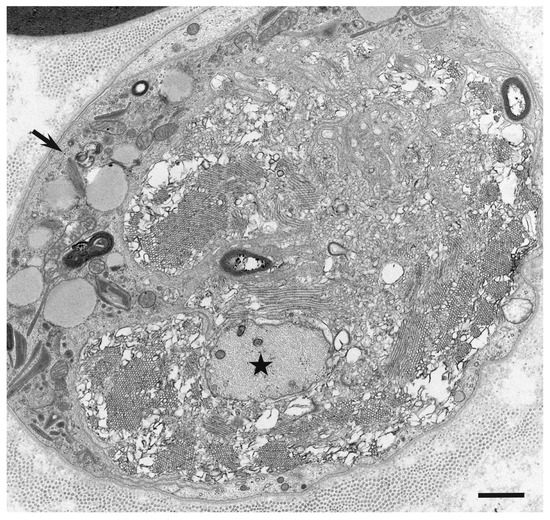

Macrophages and Autoantibodies in Demyelinating Diseases

Myelin phagocytosis by macrophages has been an essential feature of demyelinating diseases in the central and peripheral nervous systems, including Guillain–Barré syndrome (GBS), chronic inflammatory demyelinating polyneuropathy (CIDP), and multiple sclerosis (MS). The discovery of autoantibodies, including anti-ganglioside GM1 antibodies in the axonal [...] Read more.

Myelin phagocytosis by macrophages has been an essential feature of demyelinating diseases in the central and peripheral nervous systems, including Guillain–Barré syndrome (GBS), chronic inflammatory demyelinating polyneuropathy (CIDP), and multiple sclerosis (MS). The discovery of autoantibodies, including anti-ganglioside GM1 antibodies in the axonal form of GBS, anti-neurofascin 155 and anti-contactin 1 antibodies in typical and distal forms of CIDP, and anti-aquaporin 4 antibodies in neuromyelitis optica, contributed to the understanding of the disease process in a subpopulation of patients conventionally diagnosed with demyelinating diseases. However, patients with these antibodies are now considered to have independent disease entities, including acute motor axonal neuropathy, nodopathy or paranodopathy, and neuromyelitis optica spectrum disorder, because primary lesions in these diseases are distinct from those in conventional demyelinating diseases. Therefore, the mechanisms underlying demyelination caused by macrophages remain unclear. Electron microscopy studies revealed that macrophages destroy myelin as if they are the principal players in the demyelination process. Recent studies suggest that macrophages seem to select specific sites of myelinated fibers, including the nodes of Ranvier, paranodes, and internodes, for the initiation of demyelination in individual cases, indicating that specific components localized to these sites play an important role in the behavior of macrophages that initiate myelin phagocytosis. Along with the search for autoantibodies, the ultrastructural characterization of myelin phagocytosis by macrophages is a crucial step in understanding the pathophysiology of demyelinating diseases and for the future development of targeted therapies. Full article